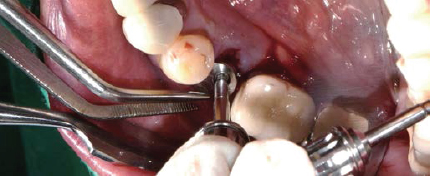

제조사의 식립순서에 맞춰 Drilling 후 Fixture 식립

Fixture 식립

Volume Up Healing Abutment 체결

제조사의 식립 순서에 맞춰 Drilling 후 Fixture 식립

-

Fixture에 Volume Up Healing Abutment 체결